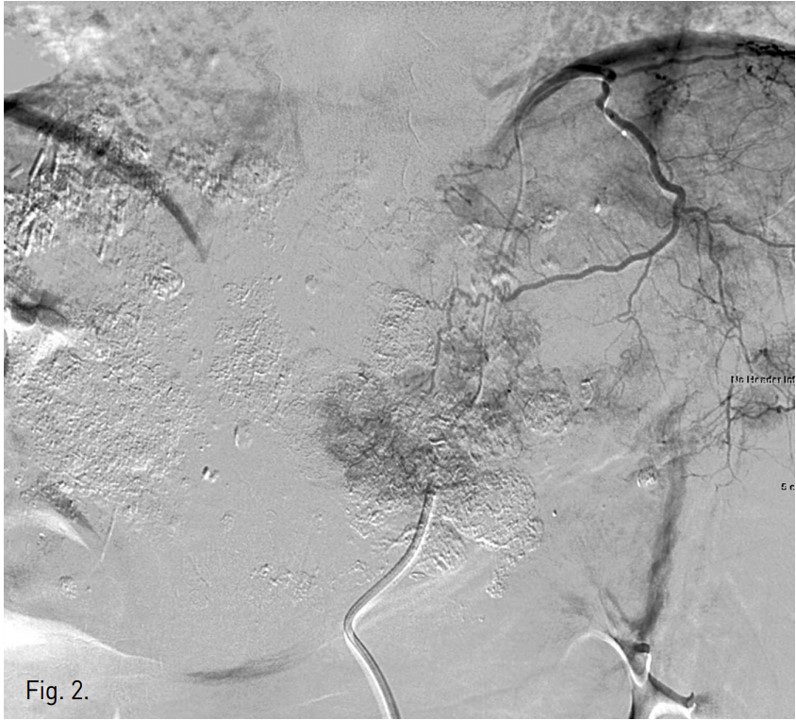

우측 대퇴동맥을 천자하여 복강동맥과 총간동맥 혈관조영술을 시행하였고 좌측 간동맥에서 혈류공급을 받는 다수의 과혈관성 종양이 관찰되었음(Fig. 1). 반복적인 TACE 후에도 CT영상에서 lipiodol defect area들이 보였기 때문에 간외측부순환에 의한 간세포암의 혈액공급 가능성이 있어 양측 횡경막하동맥과 내유방동맥 혈관조영술을 시행하였고 좌측 횡경막하동맥과 우측 내유방동맥에서 간세포암의 혈액공급이 관찰되었음(Figs. 2, 3). 이들 동맥의 혈관조영 영상에서 간정맥이나 폐혈관과의 shunt는 보이지 않았음. 2.0F 미세카테 타를 5F 카테타내 에 coaxial로 삽입하여 사용하는 동안 heparin mix 된 saline으로 카테타 flushing을 유지하였음. 각각의 간세포암 혈액 공급 혈관을 2.0F 미세카테타로 선택하여 lipiodol 13 ml와 adriamycin 60mg emulsk)n을 주입하였고,간외측부순환들은 추가적인 젤폼 색전술을 시행하였음. 색전술후 사진에서 종양내 lipiodol이 축적되고 과혈관성 종괴가 안 보이는 것을 확인한 후 시술을 마쳤음.

Fig. 1.

Fig. 1. Common hepatic arteriogram shows multiple hypervascular tumor stainings in the remnant left hepatic lobe.